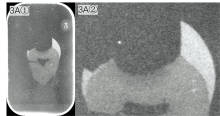

图4A①是利用时域信号最小值对应的时间成像, 图像上牙釉质、 牙本质及牙本质龋未能表现出形态上的区分, 仅能显示出样本的轮廓, 其对应的灰度图4A②表现出相似的特征。 图4B①是利用频域1 THz相位差进行成像, 其效果相较于图4A①而言更佳, 其对应的灰度图4B②牙本质龋相对于其他部分颜色要深, 形态上有一定的区分度。 图4C①是利用频域1 THz功率进行成像, 该图像上仅能显示出样本的轮廓, 其对应的灰度图效果相似。

图4(A— C)是采用90° 垂直入射的反射系统获得的图像, 仅能呈现样本轮廓, 不能有效区分牙釉质、 牙本质及牙本质龋, 这可能与反射信号较弱, 容易受到样品厚度、 表面平整度[10]以及系统噪声等影响。